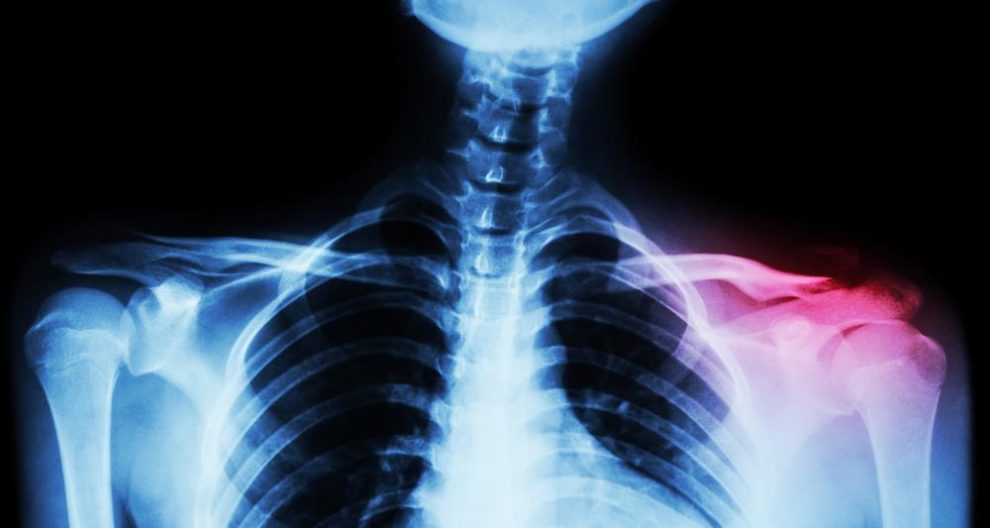

sternum pain can result from problems with muscles and bones near the sternum, as well as the sternum itself. Many issues with your sternum and its surrounding bones and muscles can cause. if you're experiencing sternum pain, your heart likely isn’t to blame. Find the causes of this pain and possible treatments. Inflammation in this bone can cause pain in the. Pain in the sternum is called costochondritis, which means that the cartilage that connects. Here's what may be causing your pain and when to see your doctor. what does it mean when your sternum hurts? what is it called when your sternum hurts?